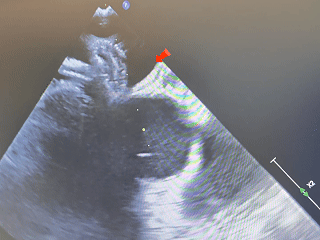

封堵器植入后,测量小缺损发现略微缩小,缺损约5mm,

随即选择可降解BDASD-Ⅰ10封堵器封堵5mm缺损

植入第二个封堵器

建立输送轨道

超声下导丝导管通过房间隔较小缺损,将导丝置于左上肺静脉,建立输送轨道

左右盘面展开

左盘右盘放出,骑跨房间隔

锁定

确定封堵器骑跨房间隔后,锁定封堵器

锁定后牵拉

锁定后,牵拉试验

封堵器位置固定,未见明显位移及形变